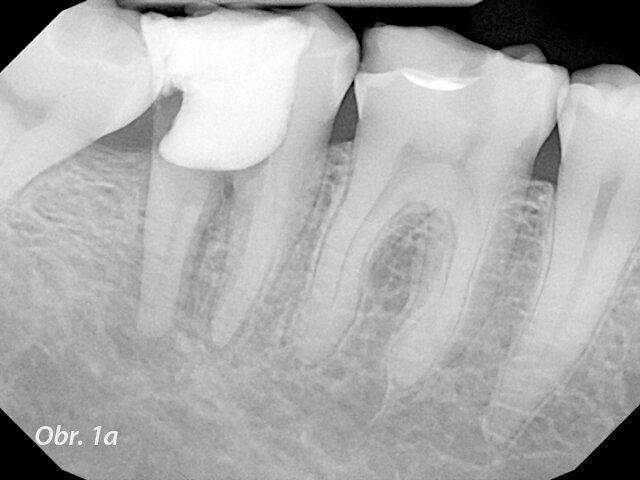

I při opracování kanálků se samozřejmě lze dopustit mnoha chyb, jako je například via falsa, perforace nebo transportace kanálku, oddělení nástroje a další. Jedna z nejvíce stresujících věcí pro ošetřujícího je perforace kanálku. Perforace v kanálku může vzniknout kvůli špatné sekvenci nástrojů, kvůli obecně špatné technice nebo kvůli technice s nadměrným třením. Pak se perforace může objevit na vnitřní straně ohybu kanálku. Když se to stane, často se setkáme s výrazným krvácením a problémy s viditelností. Situace se ještě více zkomplikuje, když se začneme zabývat staršími perforacemi spojenými s lézemi (obr. 1a–c).